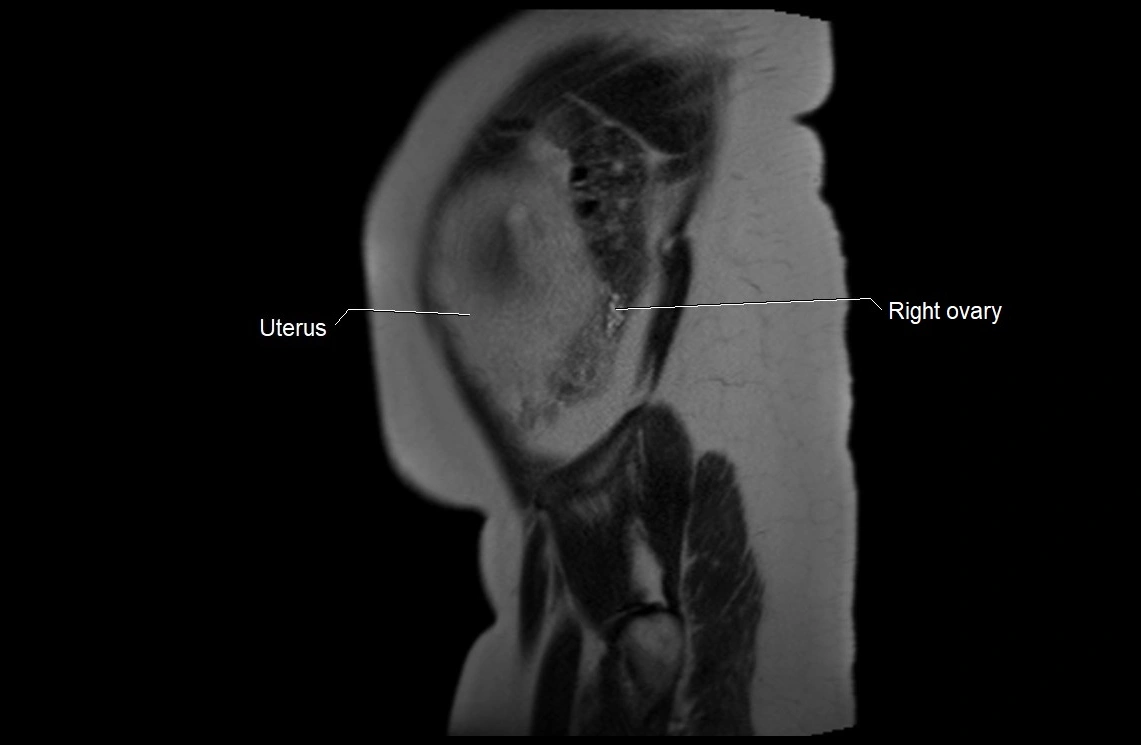

MRI Appearance

T2 HASTE (T2 GRE):

• Amniotic fluid shows very bright hyperintense signal

• Provides natural contrast against fetus and placenta

• Small particles (vernix) may appear as scattered hypointense foci within bright fluid

MRI image

image